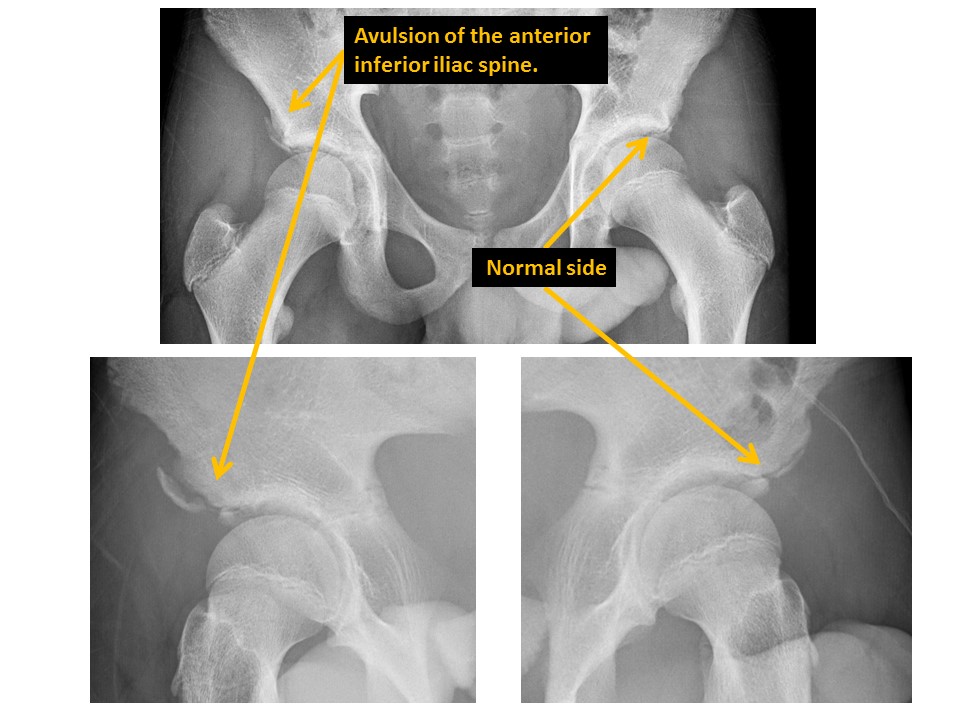

Anterior inferior iliac spine avulsion fractures are present. [Yes/No]